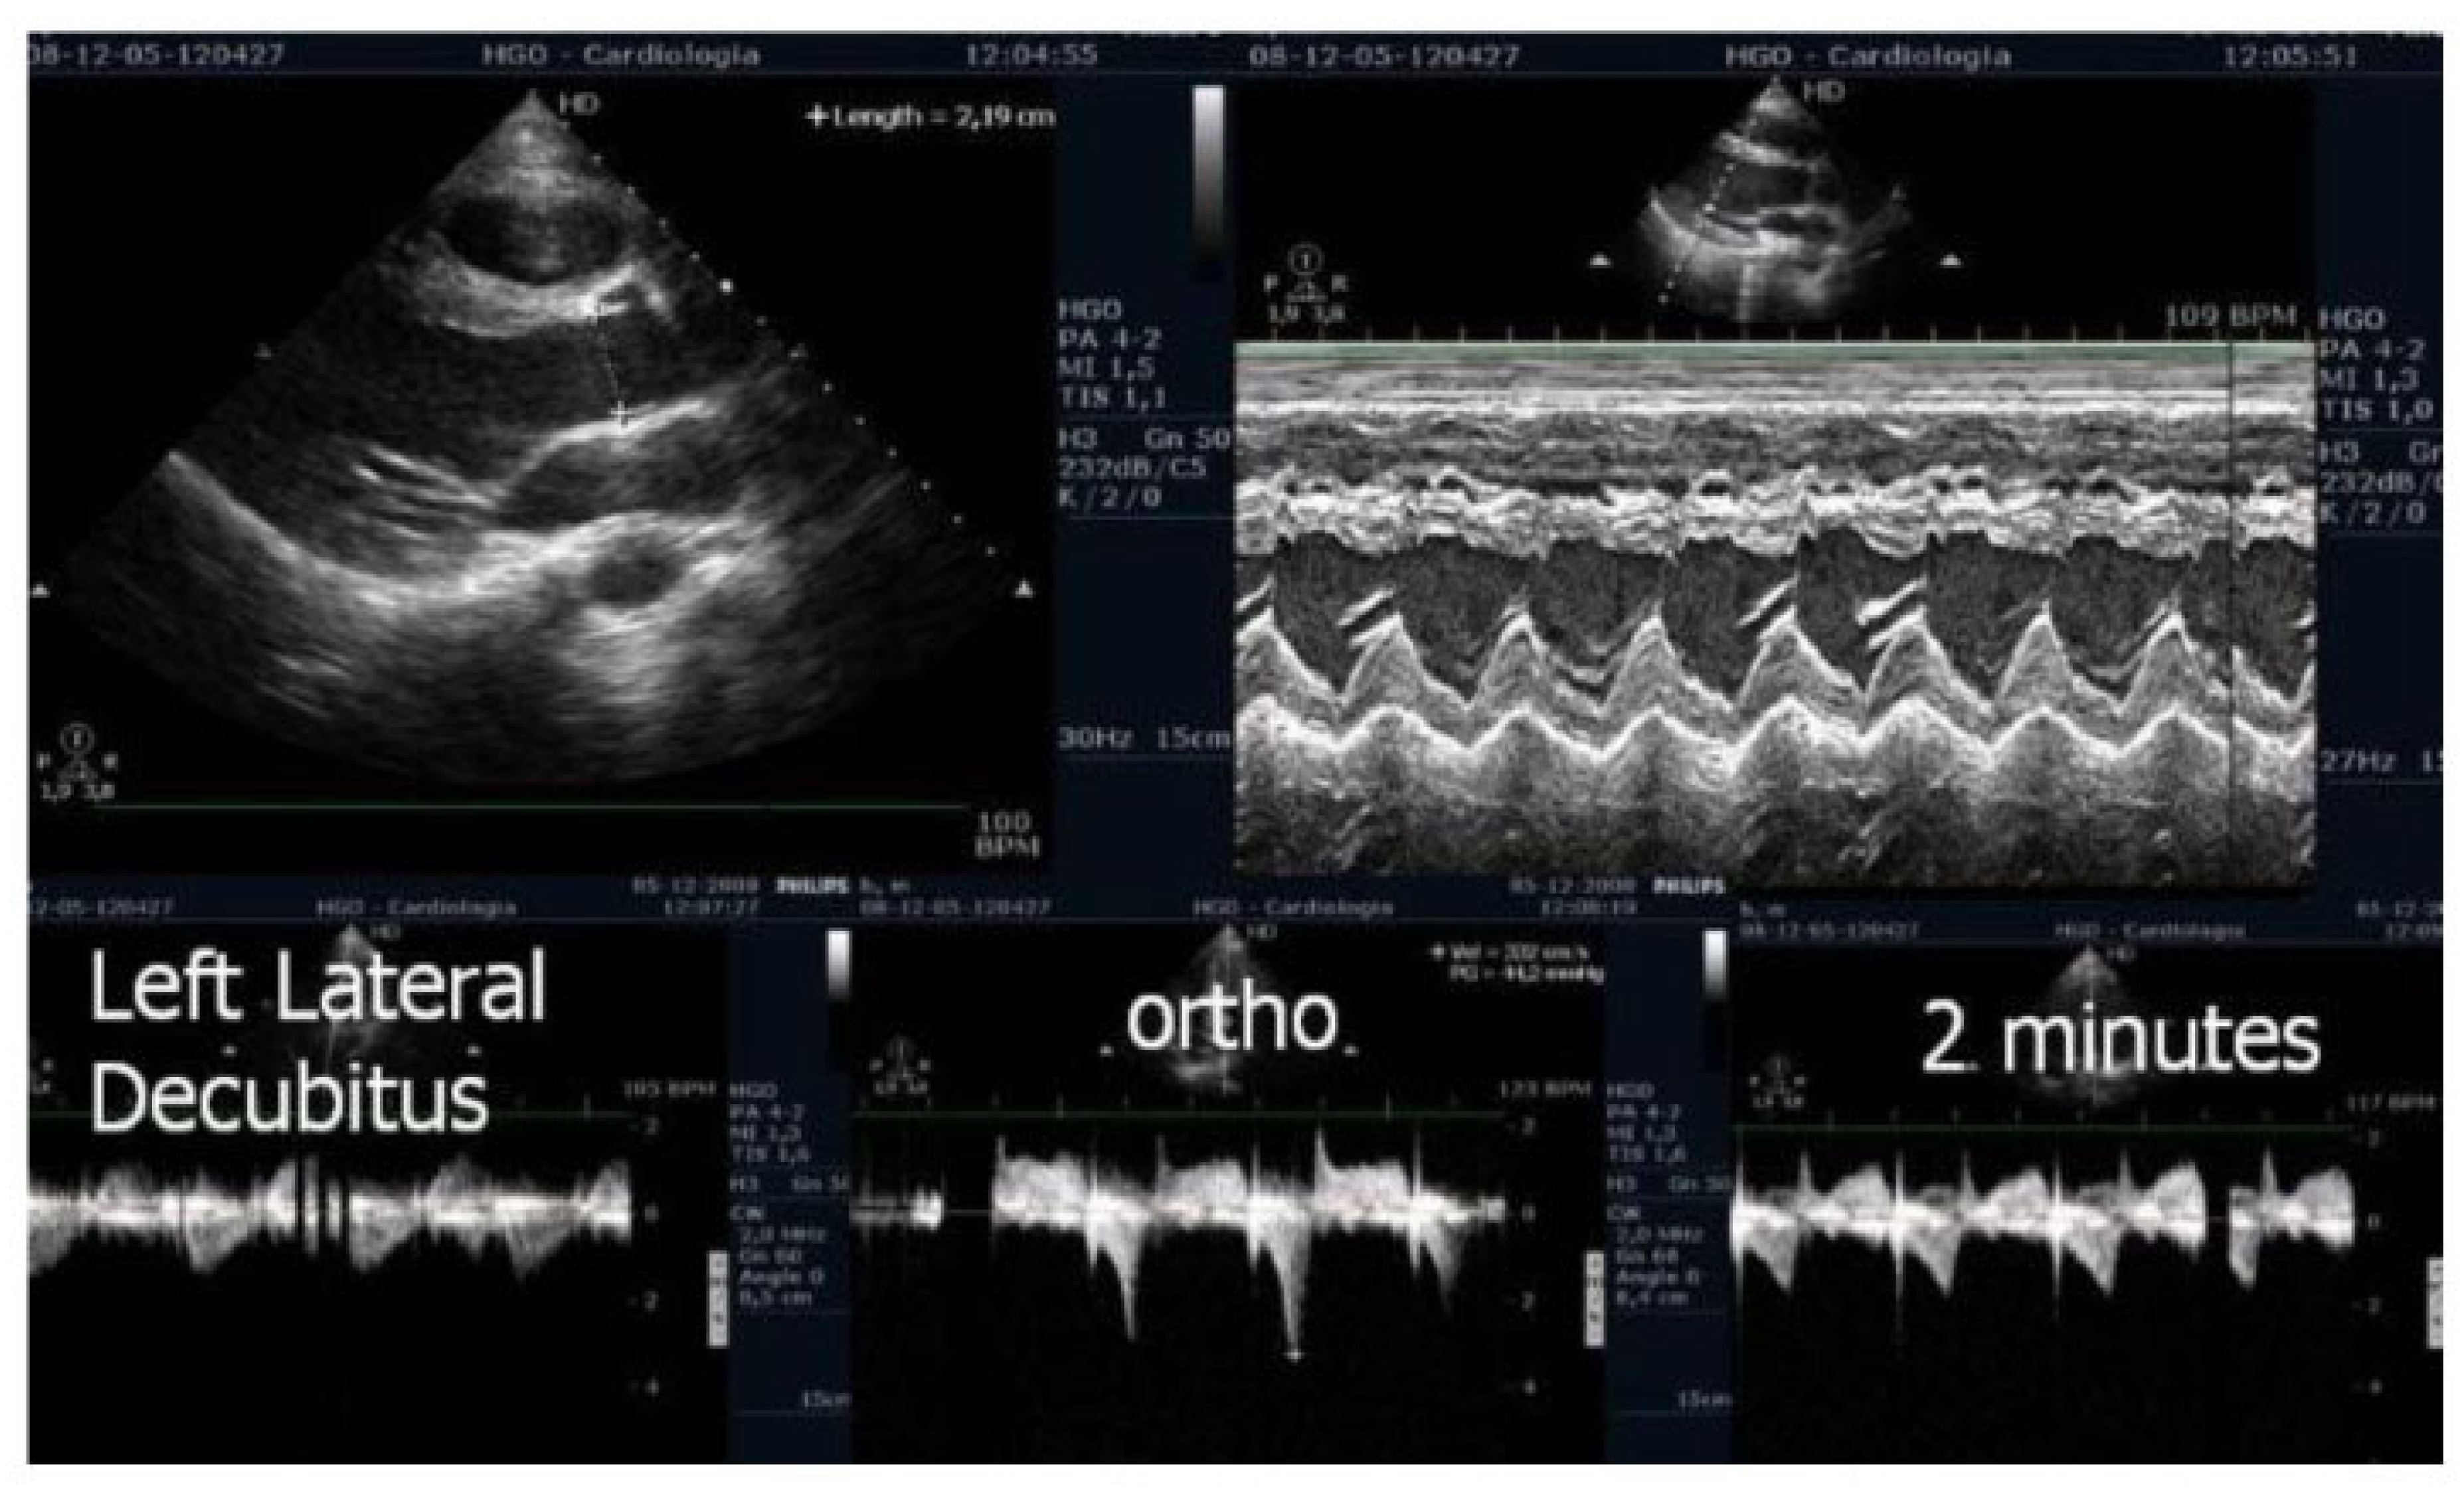

Of the 66 children enrolled in the study, 15 (23%) were female. The mean age was 14,6, 1,7 years old (11 to 17). On the resting echocardiogram, all the exams were considered normal with and without beta blockers. No wall motion abnormalities were detected in any of the exams, with or without beta blockers. IVPG (Figure 1) at peak exercise on the first assessment was 105 ± 38 mmHg, with mitral valve SAM in 28 children (Figure 2) in the complete group and 58 + 32 mmHg in only 29 children treated with beta-blockers, P< 0.0001.

Figure 1. This figure shows an intraventricular gradient during exercise in a child experiencing exercise-related chest pain and syncope, accompanied by elevated troponin levels (top). A significant reduction in the gradient is observed under beta-blocker therapy (bottom).

We observed the development of intraventricular pressure gradients (IVPGs) in children without left ventricular hypertrophy upon assuming an upright posture prior to exercise—a phenomenon previously described in patients with hypertrophic cardiomyopathy [5]. At the onset of exercise (Figure 5), the IVPG initially decreased, likely due to increased preload resulting from activation of the lower limb musculature. However, as exercise progressed, the IVPG steadily increased (Figure 6). After exercise, maintaining an upright posture led to a more pronounced reduction in preload compared to the supine position. This hemodynamic shift likely accounts for the post-exercise elevation in IVPG observed in most children studied. This postural response may also explain the orthostatic recovery IVPG observed in one highly symptomatic child who presented with exertional angina and ST-segment abnormalities (Figure 7). Additionally, Figure 8 illustrates the impact of beta-blocker therapy on ESE findings in one patient, including the titration of atenolol to a dose of 50 mg, underscoring the clinical relevance of individualized treatment.

In our study, beta-blocker therapy was associated with a reduction in heart rate, exercise-induced ST-segment alterations, systolic blood pressure, and consequently, peak heart rate–systolic blood pressure product (HR×SBP). The incidence of intraventricular gradients (IVG) (Figure 1) and systolic anterior motion (SAM) of the mitral valve (Figure 2) during exertion also decreased significantly. These hemodynamic improvements were accompanied by a notable reduction in symptoms during exercise testing and follow-up (Figure 3 and Figure 4).

Figure 5. - Echocardiography before exercise in a symptomatic child in the left lateral decubitus position and the orthostatic position before and at the beginning of exercise [5].